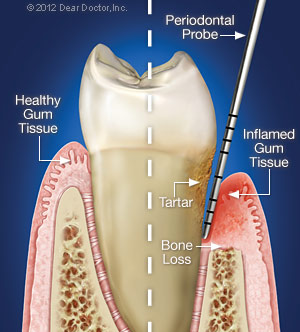

What is periodontal disease?

What are periodontal diseases? Periodontal disease is an infection in the areas around the teeth, but not in the teeth. Gingivitis is usually the first stage of periodontal disease which can progress and effect other structures in the mouth.

What is the first stage of periodontal disease?

The first stage of periodontal disease, called gingivitis, only affects the gums. Symptoms of gingivitis may include bleeding and swollen gums, bad breath, pain when chewing, and recession of the gums. If left untreated, gingivitis can advance to the other structures in the mouth and overtime, cause tooth or bone loss.

Is periodontal disease a bone disease?

This can include the gums , tissues, and/or bones of the mouth.